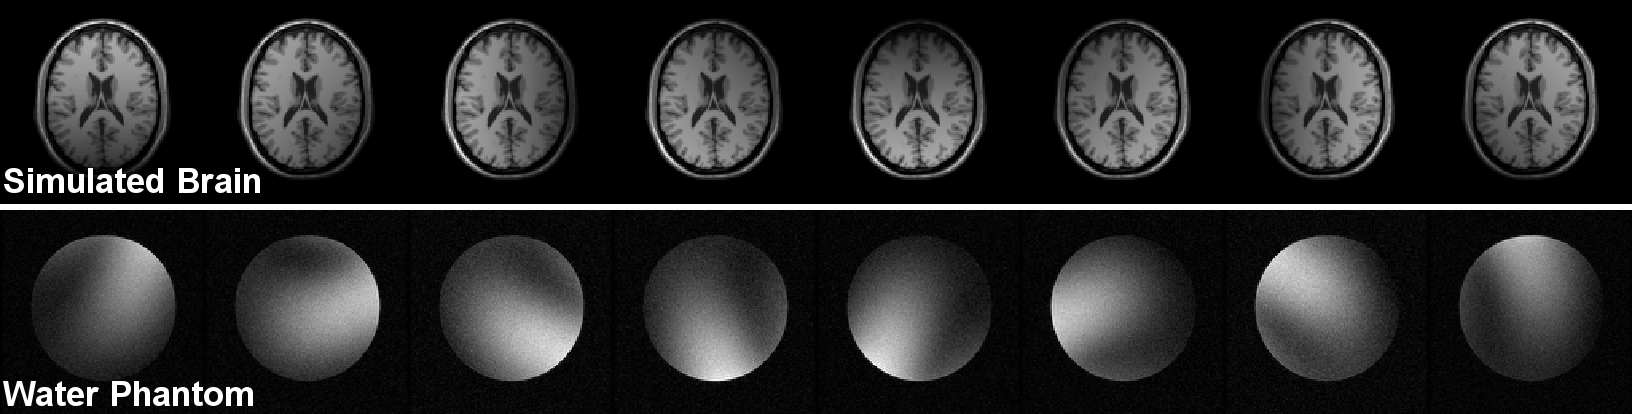

Two data sets are considered for the experiments (see Fig.ย 4):

• โ€ข

Simulated brain dataset: a reference axial brain MR image was obtained from the BrainWeb databaseย [20]. This is a T1-weighted image, with intensity non-uniformity set to INU=0%, slice thickness=1 mm and intensity range normalized to [0,255]. An L๐ฟL-coil acquisition was simulated by modulating the image using artificial sensitivity maps coded for each coil [1, 21]. The noise-free coil images were transformed into the ๐’Œ๐’Œ\bm{k}โ€“space and corrupted with synthetic Gaussian noise characterized by the matrices ฮ“ksubscriptฮ“๐‘˜\Gamma_{k} and Cksubscript๐ถ๐‘˜C_{k} with SNR=30 for each coil, and the correlation coefficient between coils was set to ฯ=0.1๐œŒ0.1\rho=0.1. For statistical purposes, 4000 realizations of each image were used.

Water phantom acquisition: 100 realizations of the same fully-encoded slice of a water phantom doped with 3.36853.36853.3685 g/L of nickel chloride hydrate (NiCl2-6H2O) and 2.42.42.4g/L of sodium chloride (NaCl), scanned in an 8-channel head coil on a 3.0T scanner (MR750, GE Healthcare, Waukesha, WI). Acquisition parameters included: TE/TR=2.0/11.8ms, flip angle=3โˆ˜, FOV=220x220mm2, matrix size=128x128, slice thickness=3mm, bandwidth=ยฑplus-or-minus\pm62.5KHz, total scan time=641.2 seconds. In order to ensure steady-state, we acquired 200 realizations and discarded the first 100. Also, we corrected for B0 field drift related phase variations by pre-processing step that estimated the phase-shift between realizations from the center of the ๐’Œ๐’Œ\bm{k}โ€“space as a cubic function of time and removed it afterwards.

Refer to caption

Figure 4: Data sets for the experiments.